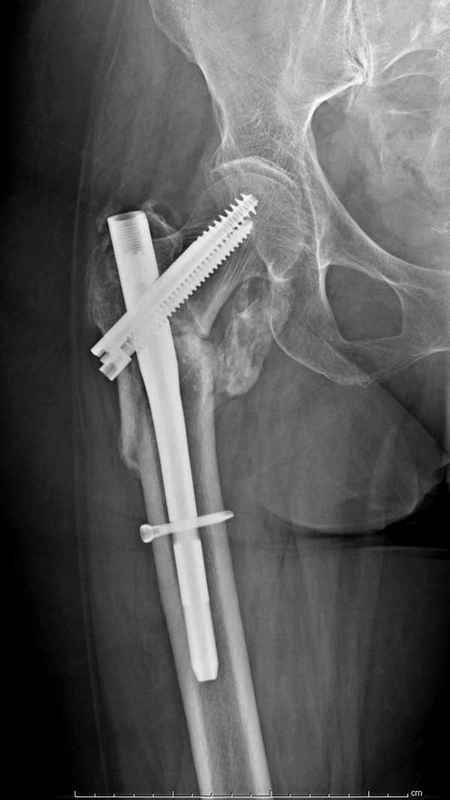

Здесь пара случаев фиксации похожих переломов:

первый высокоэнергетическая травма 36 лет

Djoldas Kuldjanov, M.D.

Department of Orthopedic Surgery

St. Louis University